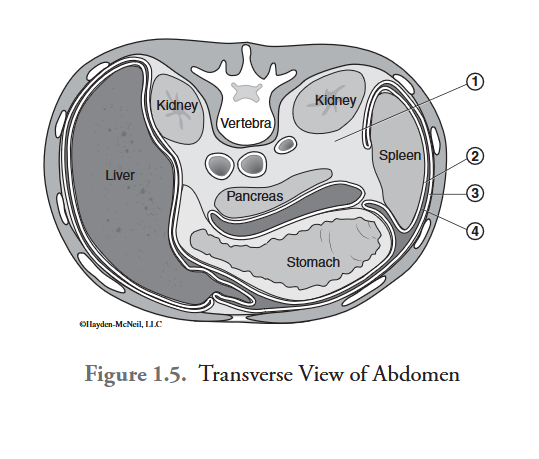

What is labeled #1?

retroperitoneal space

What is labeled #2?

visceral peritoneum

What is labeled #3?

parietal peritoneum

What is labeled #4?

peritoneal cavity